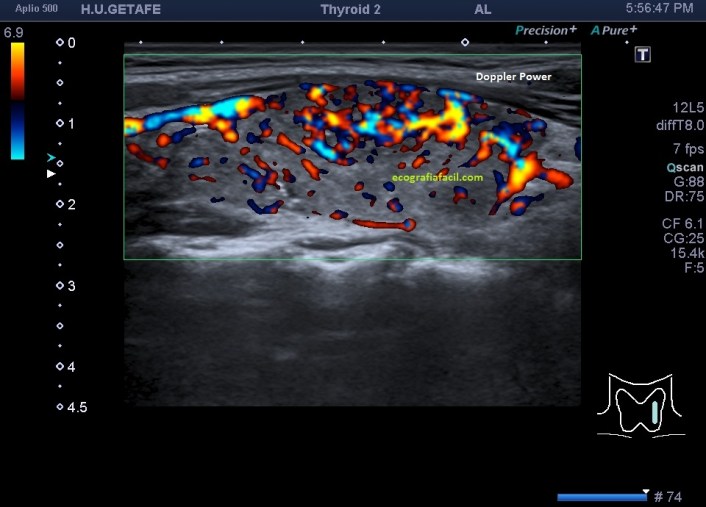

Cuando estudiamos concienzudamente la ecoarquitectura del Tiroides es momento de estudiar su apariencia vascular y descubro esto inmediatamente que me llama poderosamente la atención y que ves en la imagen 5, mira:

5

En la imagen 6 observas la misma imagen con el modo angio activado (doppler power), con el que vamos a conseguir observar la vascularización de flujo lento, por eso en el mismo corte puedes ver como si hubiera más vascularización que ves en la imagen 5.

6